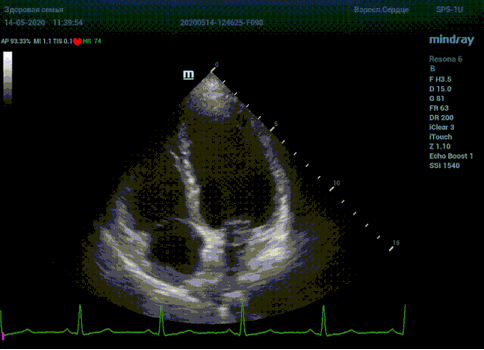

С появлением В режима реализовалась возможность визуализации всех сегментов миокарда из парастернальных и апикальных сечений. Метод Teicholtz в широкой практике сменился методом дисков. Метод дисков, или метод Simpson, позволяет разбить левый желудочек на 20 дисков, с расчетом объема каждого из них. Используя 2 перпендикулярных сечения, апикальные двух и четырех камерное, мы приближаемся к значению реального объема левого желудочка. Исследователь обводит интерфейс эндокард – кровь в фазу диастолы и фазу систолы. Линия простирается от кольца митрального клапана и до кольца митрального клапана, четко разграничивая объем желудочка от предсердия. Для достоверного изменения необходимо использовать ЭКГ канал.

Что могут предложить современные приборы? Приборы нашего времени являются мощными вычислительными машинами, способными обрабатывать полученную информацию даже без помощи человека. Система автоматического вычисления фракции выброса – AUTO EF на приборах серии Resona компании Mindray сделает все за вас. За пару секунд прибор сам отыщет нужную фазу сердечного цикла и произведёт измерение и расчеты, а также покажет график изменения объема в сердечном цикле. От Вас требуется только получить качественное 4С и 2С сечение. Впрочем, прибор всегда оставляет возможность коррекции, если доктор имеет свое мнение на расположение точек планиметрии или момента измерения по ЭКГ каналу.